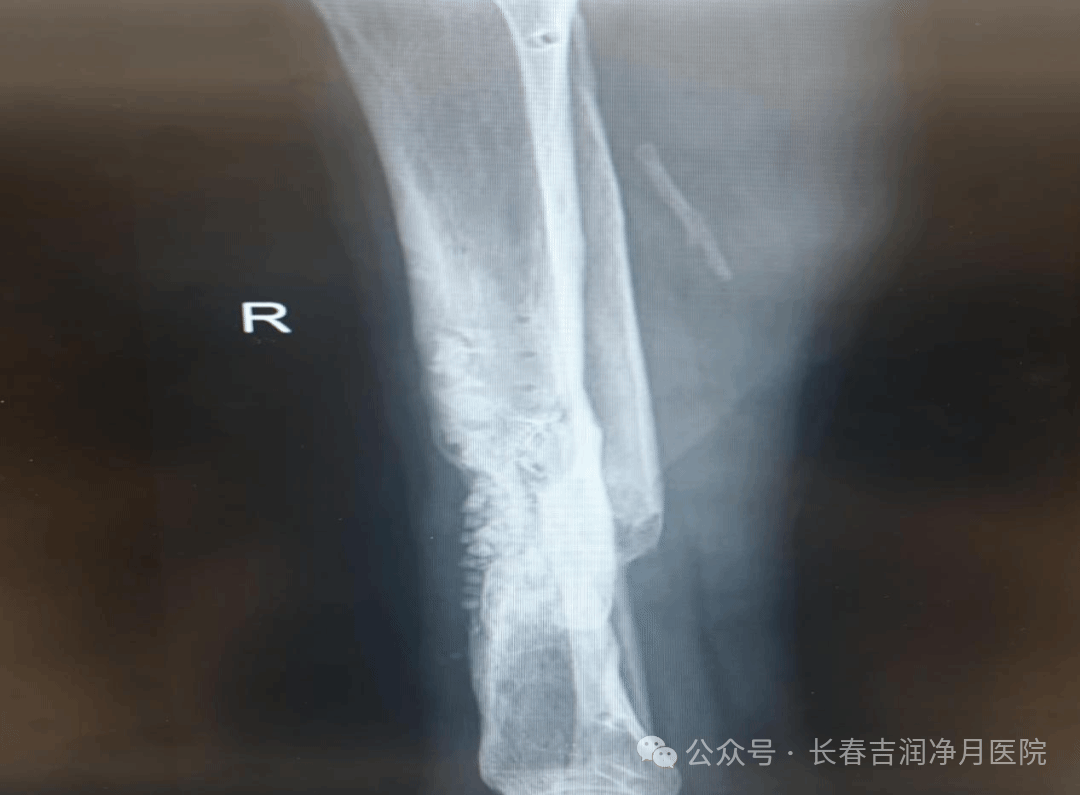

(于铁成主任团队第一次术后两次复查片)